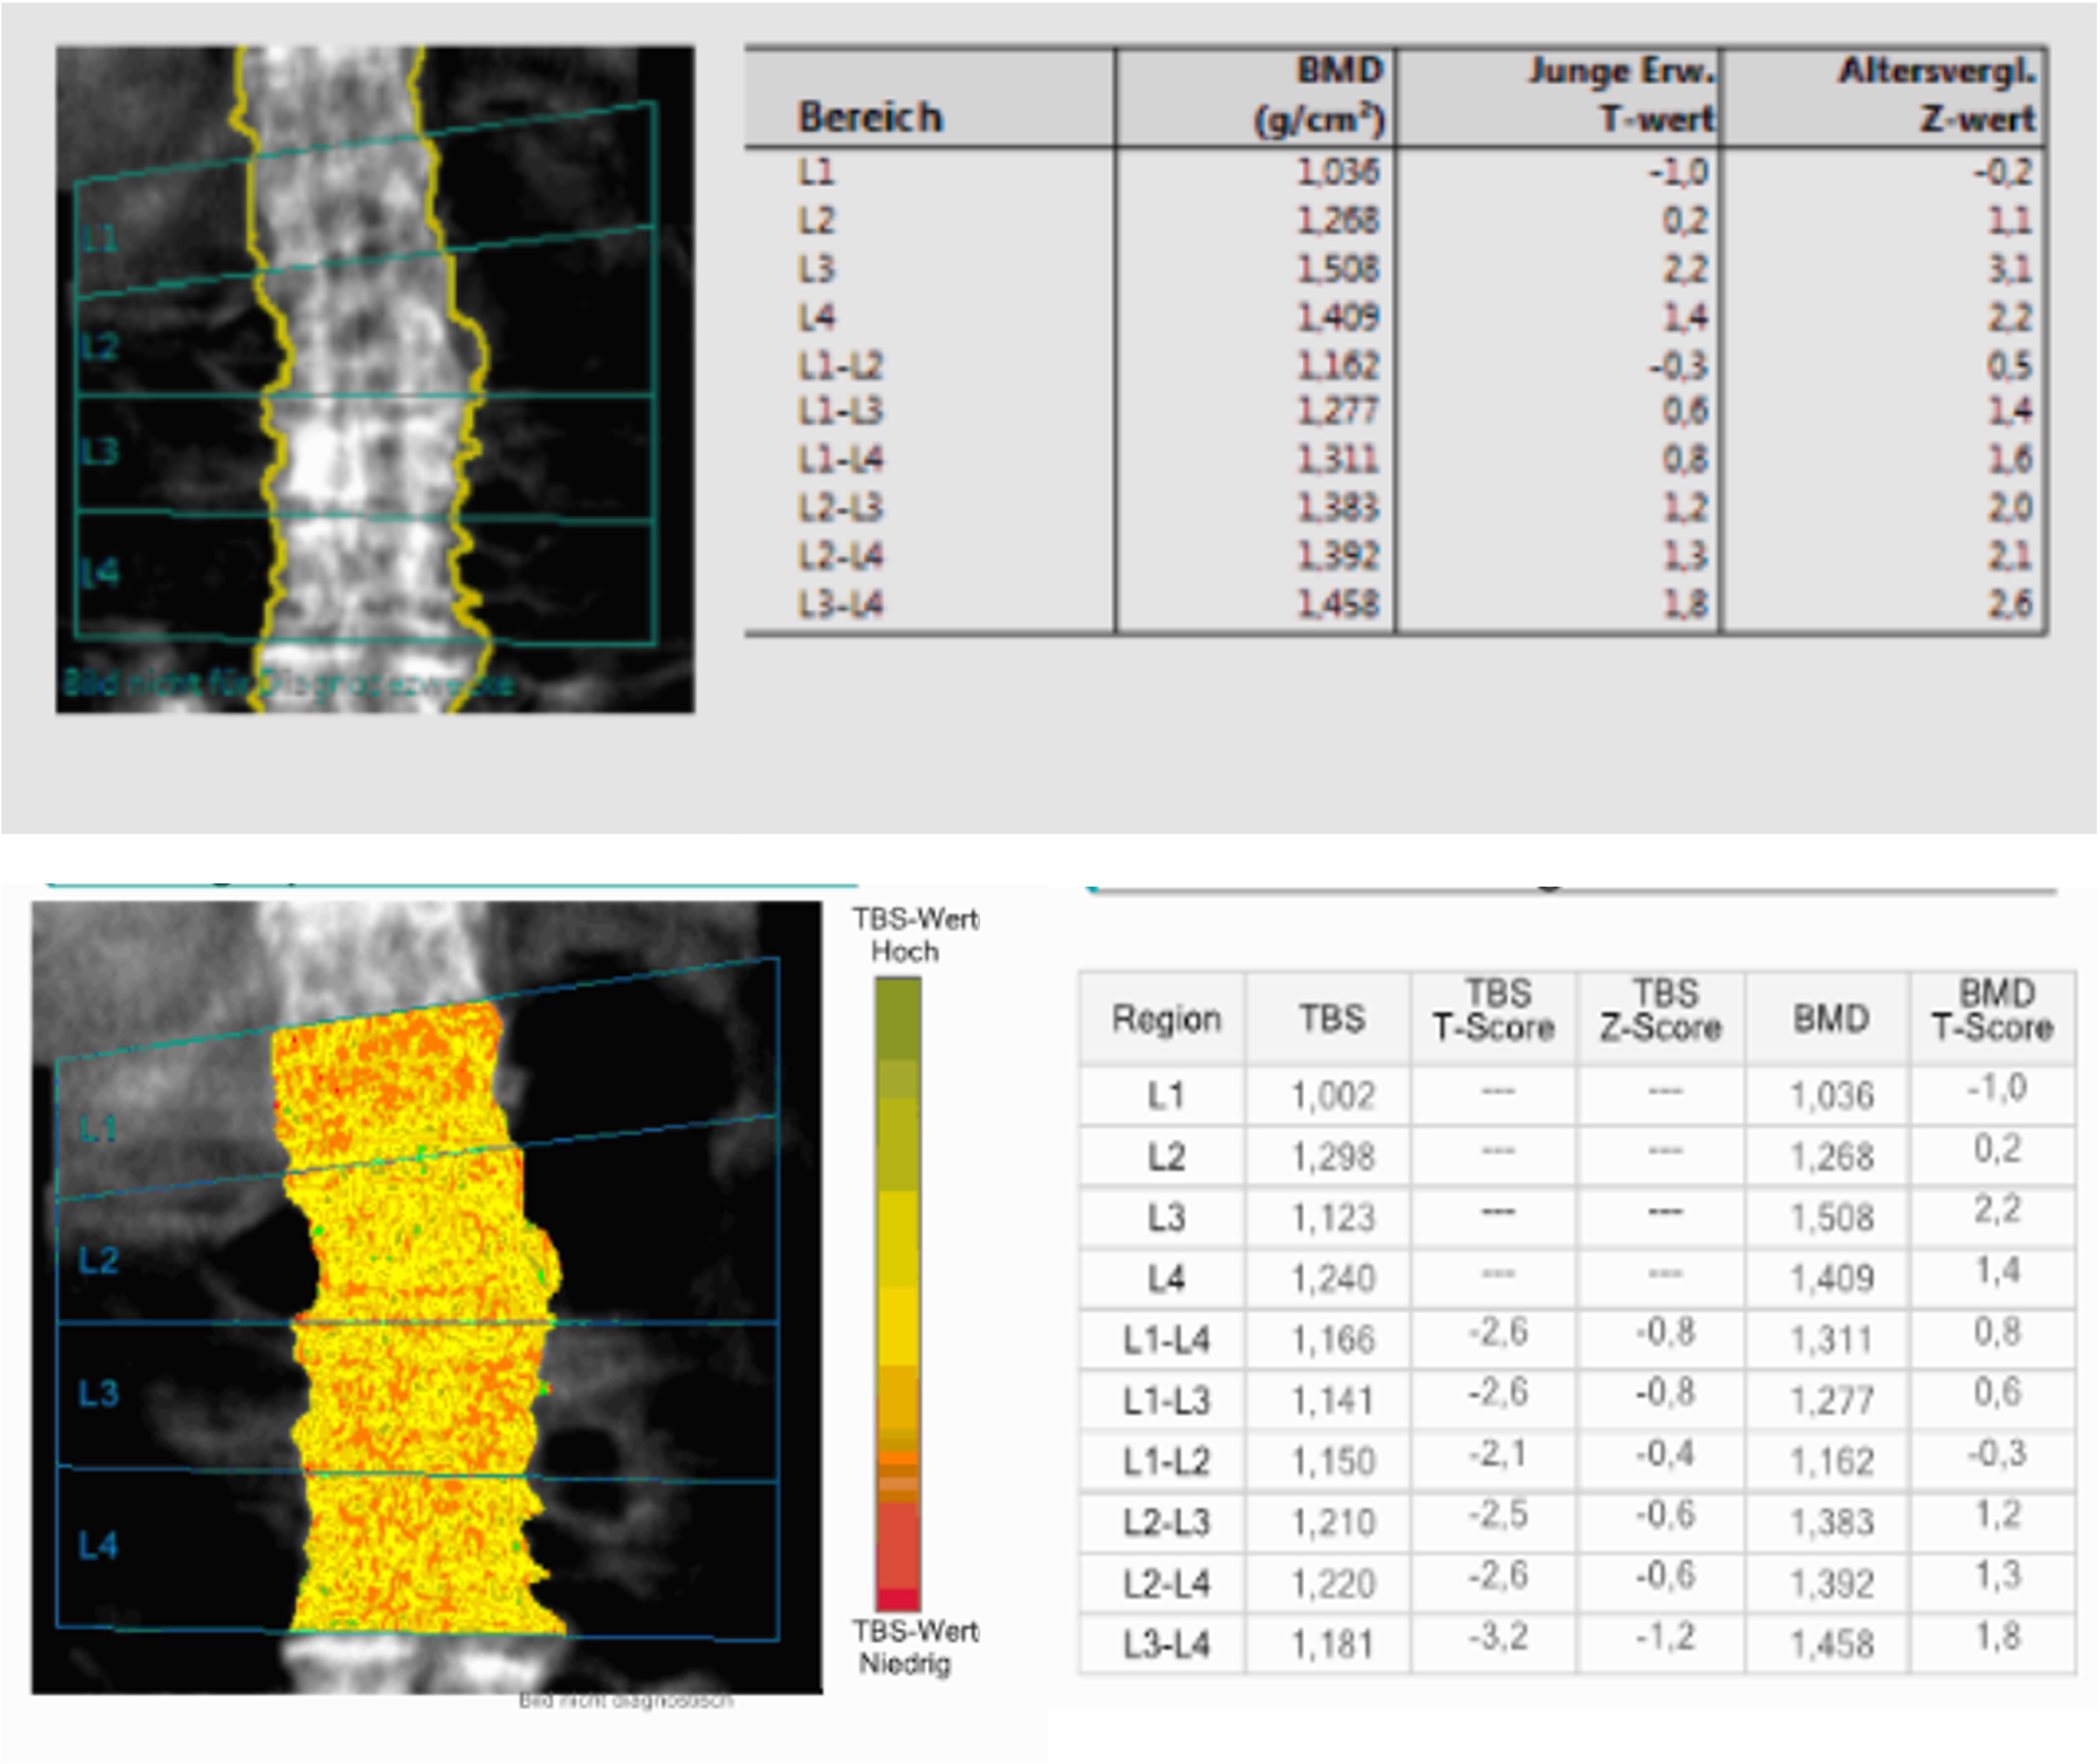

Example of the differences between DXA BMD T-Score (top) and TBS (bottom) in the same patient with DISH